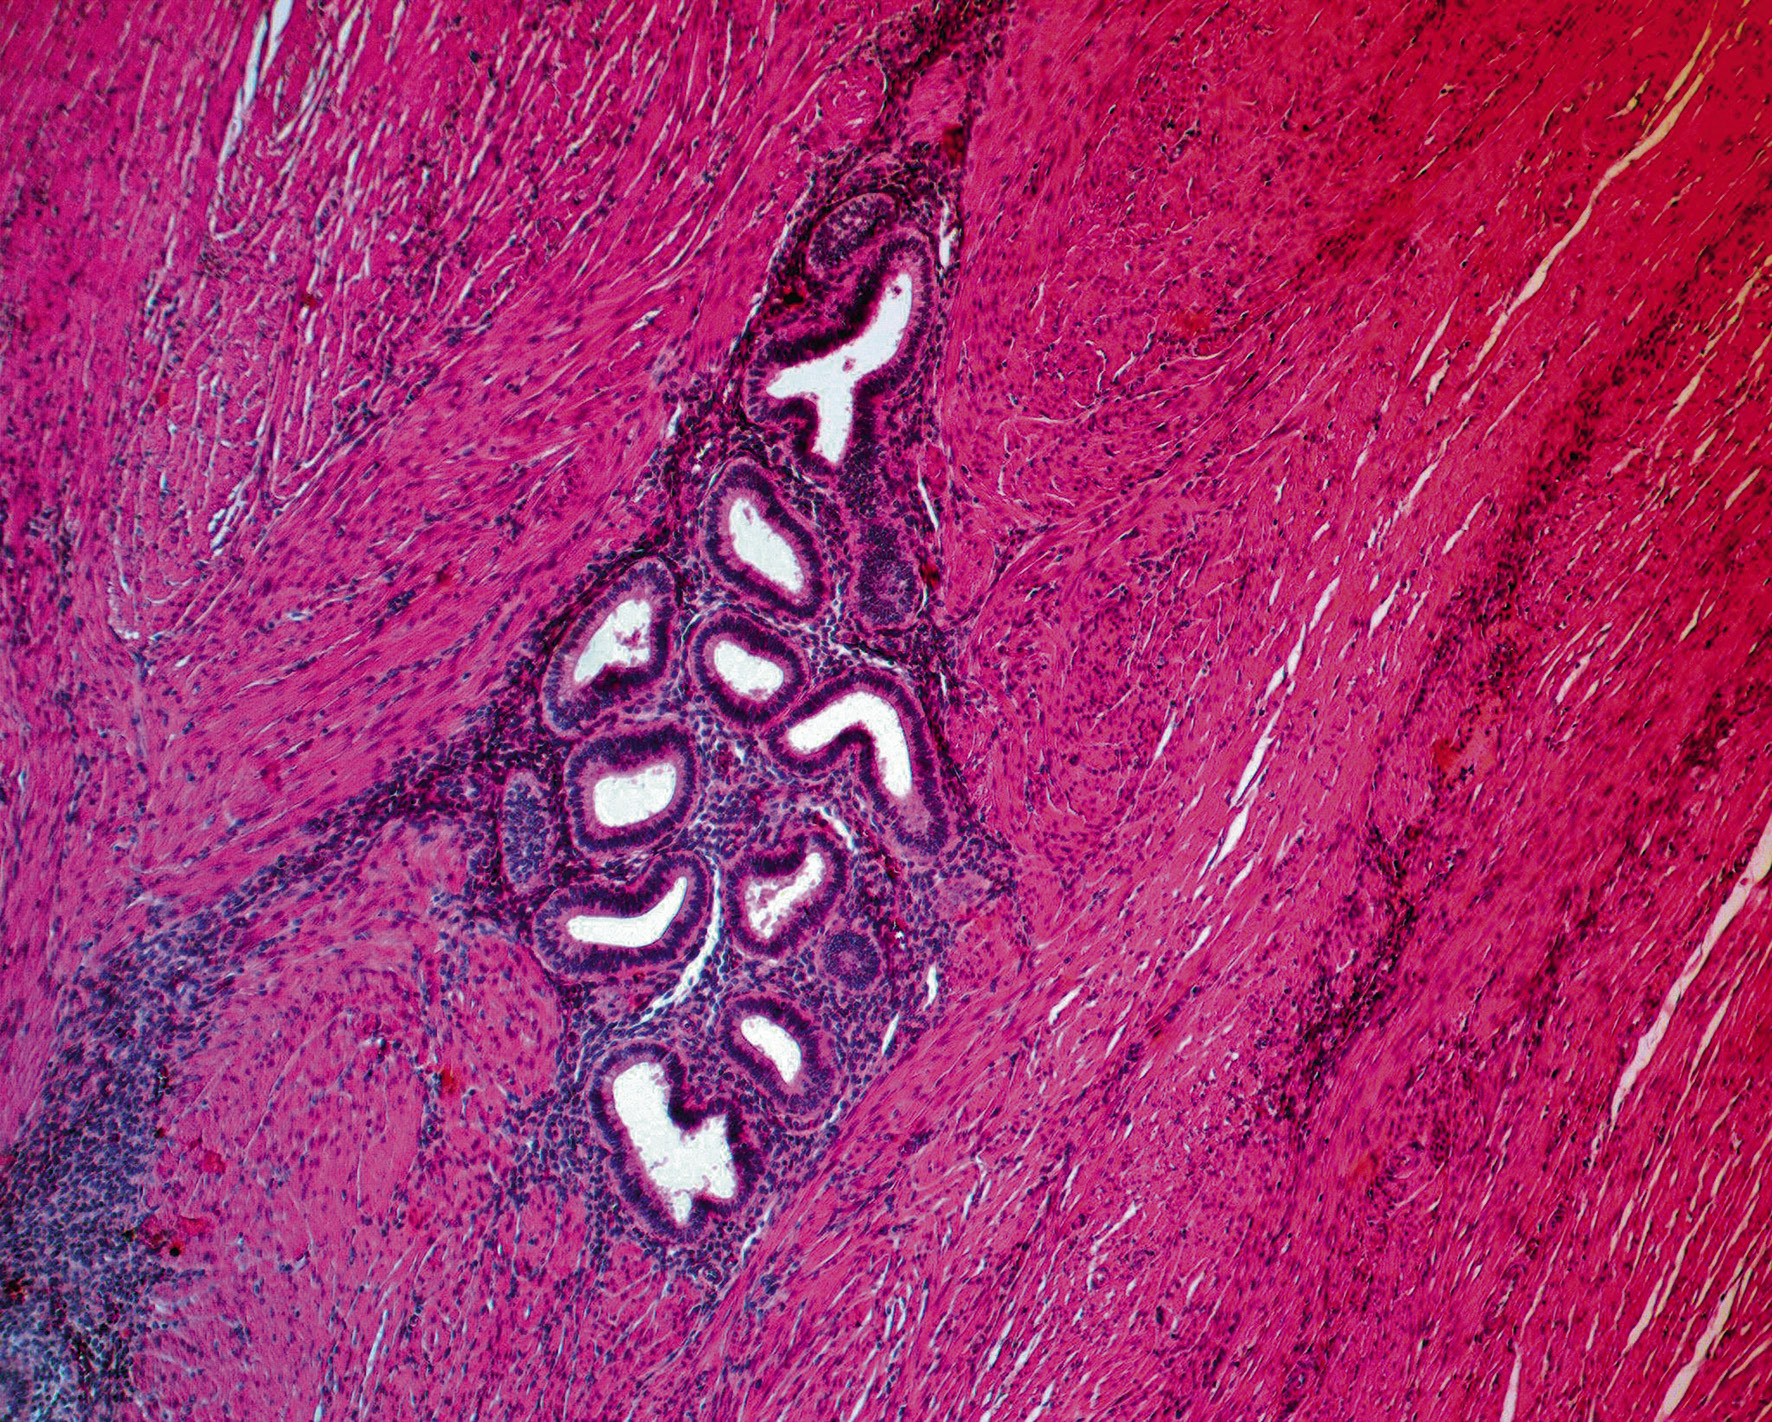

При микроскопическом исследовании фрагментов из измененных участков стенки тонкой кишки и мышечного слоя стенки аппендикса видны множественные диффузно расположенные очаги эндометриоза эпителиально-стромального строения, представленные цитогенной стромой и железами, выстланными однорядным эндометриальным эпителием (рис. 4).

Рис. 4. Очаг эндометриоза в мышечном слое стенки тонкой кишки. Окраска гематоксилином и эозином, ув. ×180 / Fig. 4. Endometriosis focus in the muscular layer of the wall of the small intestine. Hematoxylin-eosin stain, enl. ×180 times

В большинстве эндометриоидных гетеротопий были признаки морфофункциональной активности в виде пролиферативных (рис. 5) и секреторных изменений (рис. 6) как эпителия желез, так и клеток цитогенной стромы.

Рис. 5. Очаг эндометриоза в мышечном слое стенки тонкой кишки с пролиферативными изменениями эпителия желез и клеток цитогенной стромы. Окраска гематоксилином и эозином, ув. ×180 / Fig. 5. Endometriosis focus in the muscular layer of the wall of the small intestine with proliferative changes in the glands and cells epithelium of the cytogenic stroma. Hematoxylin-eosin stain, enl. ×180 time